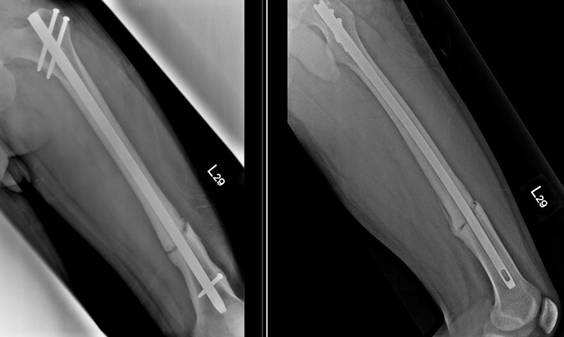

【108-2 醫學(五) 第57題】一位32歲男性左股骨幹骨折(femoral shaft fracture),手術後2年半,仍時常感到左大腿疼痛,無法負重行走,其X光檢查結果如下圖。下列敘述何者錯誤?